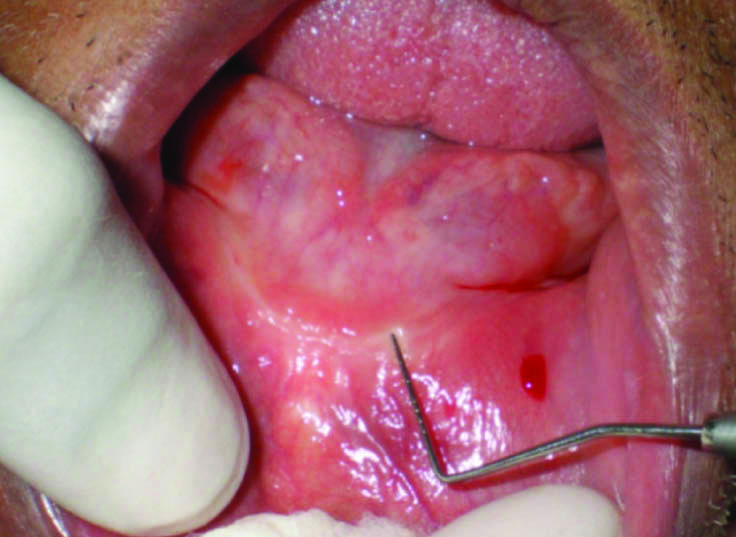

1) Surgical Procedure: The mandibular anterior region with deficient keratinized mucosa was measured using William’s periodontal probe [Table/Fig-3]. The maxillary ridge crest was found with adequate soft tissue thickness with appropriate ridge dimensions thus the palato-lateral slope of right maxillary ridge approximately 2-4 mm below the crest was selected as donor site for connective tissue graft. The patient was anesthetized locally with lignocaine 2% associated with epinephrine in concentration of 1:100,000. A mucoperiosteal incision with adequate antero-posterior extension was given on donor site to raise a partial-thickness flap using Bard-Parker blade no. 15. A free gingival graft was obtained from the donor site with minimal bleeding at the surgical site [Table/Fig-4,5]. The gingival graft was placed over the surgical area and fixed by compression sutures using absorbable thread (Vicryl suture) to remain stable and in close contact with the periosteal bed [Table/Fig-6,7]. The maxillary ridge donor sites were sutured using 4-0 silk threads to promote haemostasis and clot stabilization. Postoperative care included a 0.12% chlorhexidine rinse twice daily for two weeks, 500 mg of amoxicillin three times a day for seven days, 100 mg of Nimesulide two times a day for three days, and 500 mg of paracetamol as needed for pain. The suture removal was done after 14 days where the donor and recipient site presented eventful healing without any postoperative discomfort.

Measuring deficient site with William’s periodontal probe.